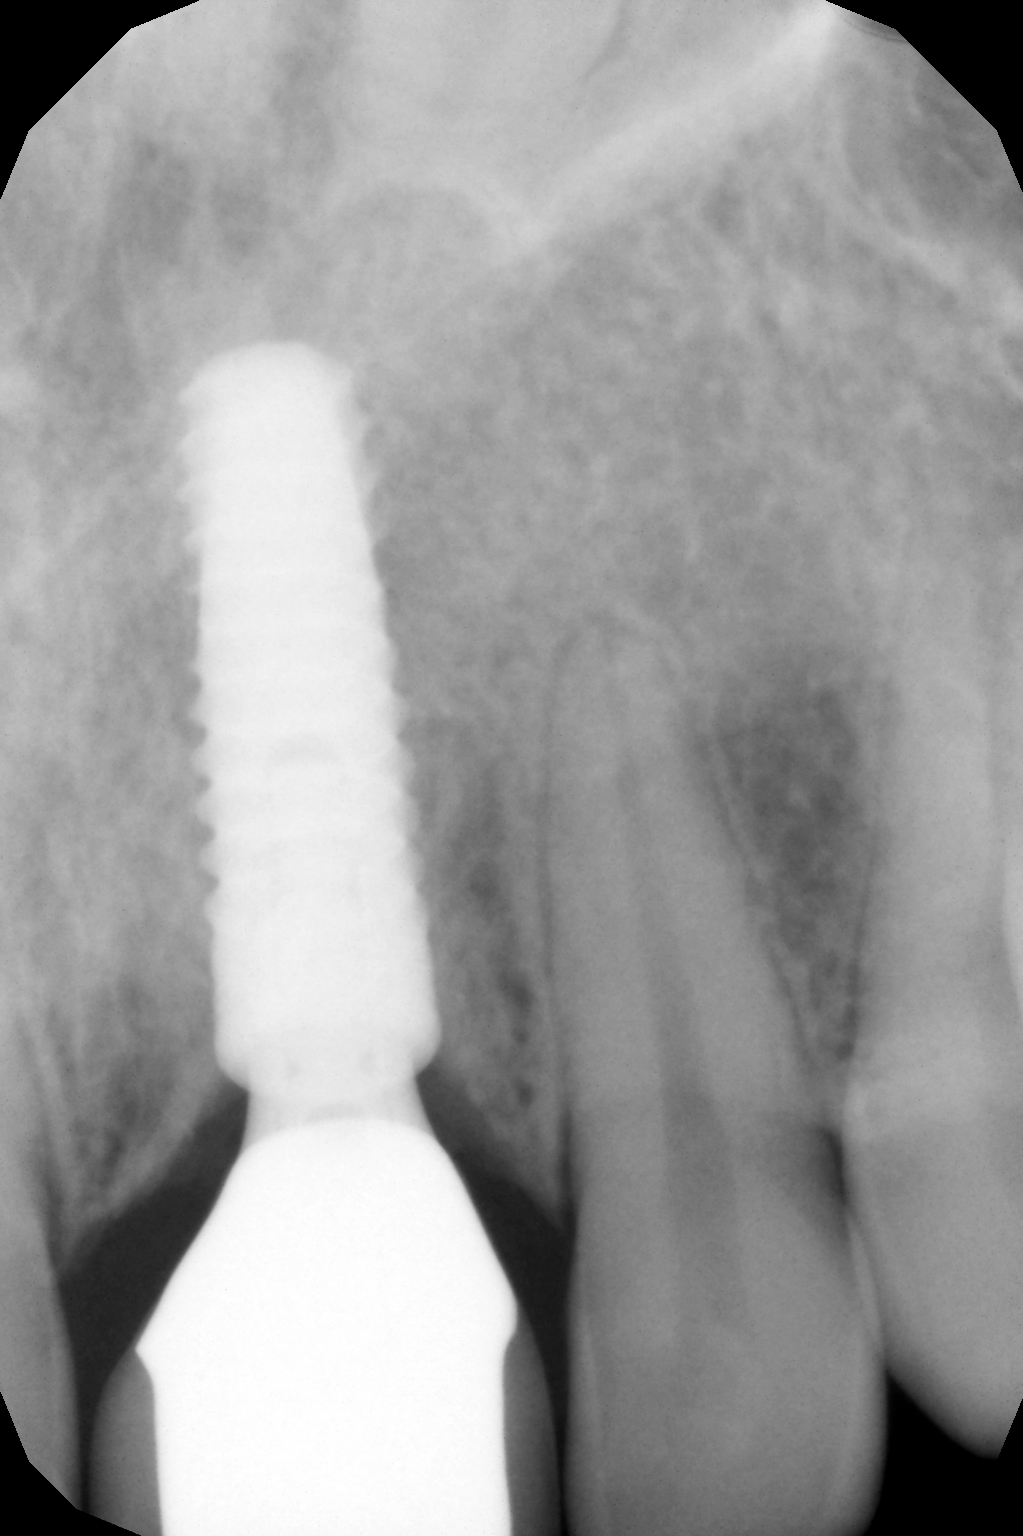

Der Mukoperiostlappen wurde palatinal angehoben und teilweise vestibulär mobilisiert. Ein 14 mm langes Implantat BioniQ® von LASAK mit Ø 4 mm wurde eingesetzt und nach dem Entfernen des Trägers ein provisorischer Aufbaupfosten befestigt.

Das Röntgenbild nach drei Jahren zeigt ebenfalls eine verheilte Alveole ohne resorptive Veränderungen.